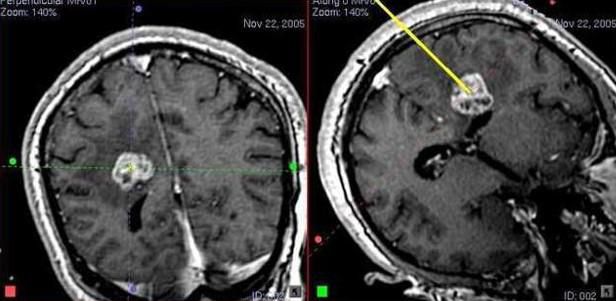

ЕХО-ЕС – при відсутності КТ, МРТ. Провідними методами діагностики є КТ і МРТ головного мозку. Комп’ютерна томографія в основному проводиться в гострий період травми тому, що краще візуалізується скупчення крові між дуральною оболонкою та мозком.

При хронічній субдуральній гематомі для діагностики перевагу віддають МРТ.